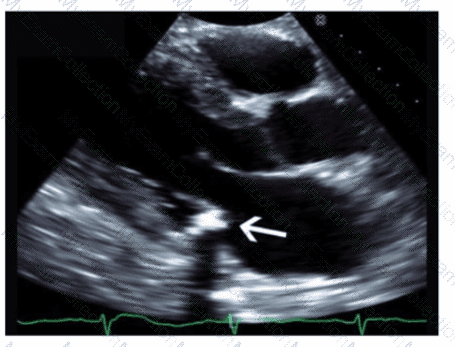

Which left ventricular regional wall segment is indicated by the arrow on this image?